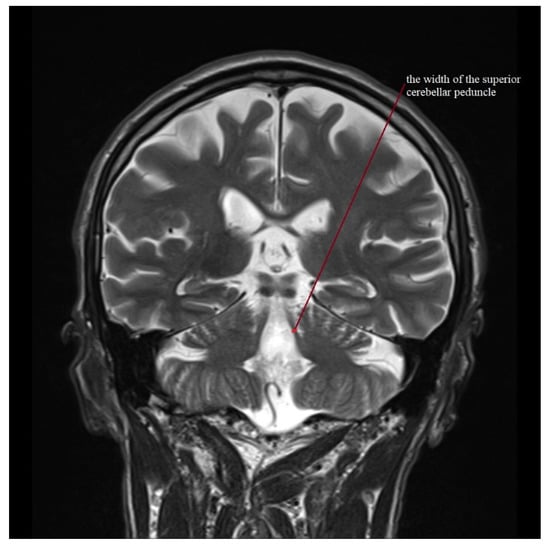

| MRPI | 11.247 (7.758–15.429) | 1.882 ± 1.39–2.912 | 17.384 (12.025–26.626) | 4.439 ± 3.183–7.327 | 19.366 (9.343–31.303) | 6.944 ± 5.247–10.27 | 10.766 (7.163–17.151) | 2.503 ± 1.915–3.614 | 15.363 (6.582–29.025) | 5.03 ± 3.801–7.439 |

| MRPI 2.0 | 2.342 (1.252–3.463) | 0.619 ± 0.457–0.958 | 4.338 (2.526–6.306) | 1.344 ± 0.964–2.219 | 5.646 (2.595–9.838) | 2.324 ± 1.756–3.436 | 2.558 (1.41–4.549) | 0.91 ± 0.696–1.314 | 4.195 (1.953–9.285) | 1.686 ± 1.274–2.493 |